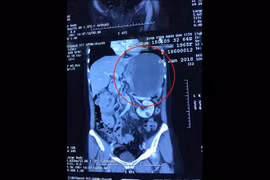

Chiều 17-6, Bệnh viện Đa khoa Xuyên Á (BVXA) thông tin đã phẫu thuật thành công cắt khối u trung thất (u ở phần lồng ngực giữa hai lá phổi) kích thước rất lớn 13x15x18 cm.